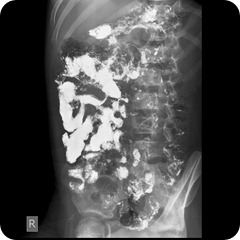

Berikut hasil pemeriksaan appendicografi manakah yang benar dan manakah yang positif apendisitis.

beberapa contoh gambar diatas adalah pemeriksaan radiologi apendicografi yang kurang optimal.

beberapa faktor yang mengakibatkan tidak optimaal adalah karena persiapan pasien yang tidak memenuhi perintah dari radiografer, informasi radiografer yang kurang jelas, informasi radiografer dalam memberikan takaran barium sulfat kurang jelas.